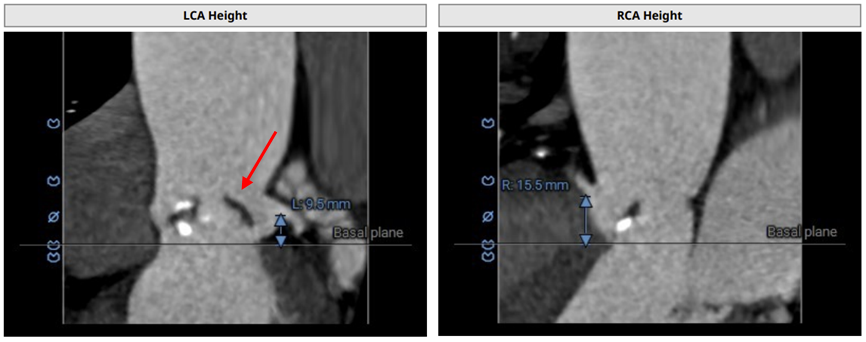

术前CT评估:

CT分析提示:TypeI型二叶瓣,左右瓣叶融合,瓣叶增厚,重度偏心性钙化,钙化位于无冠瓣叶及右无瓣叶交界处,且钙化延伸至LVOT2.5mm,舒张期可见瓣叶关闭不全间隙,右冠高度可,左冠开口平面可见瓣叶,左冠堵塞风险极高,心室略大,室壁厚度可,非横位心,升主动脉瘤样扩张,大血管走行自然,右侧髂总动脉血管细小。

瓣环直径29mm,LVOT直径31.1mm,typeI型瓣叶且偏心钙化位于无冠窦,按照常规瓣膜型号选择标准,但考虑患者两叶瓣,且左冠状动脉阻塞风险极高,downsize选择瓣膜型号,拟植入26mmVenus-A,备29mmVenus-A,高位释放,采用可回收输送系统,术中22mm球囊预扩张sizing后确定最终瓣膜型号选择。左冠预置支架保护。以左侧股动脉为主入路。